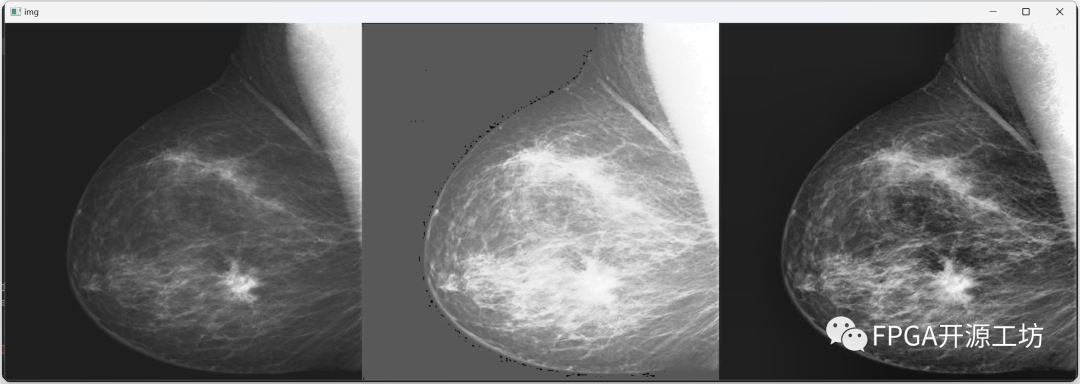

最左侧为原图,中间为直方图均衡化后的结果,最右侧为CLAHE算法的效果。

从视觉效果上来看,CLAHE算法的效果最为明显。